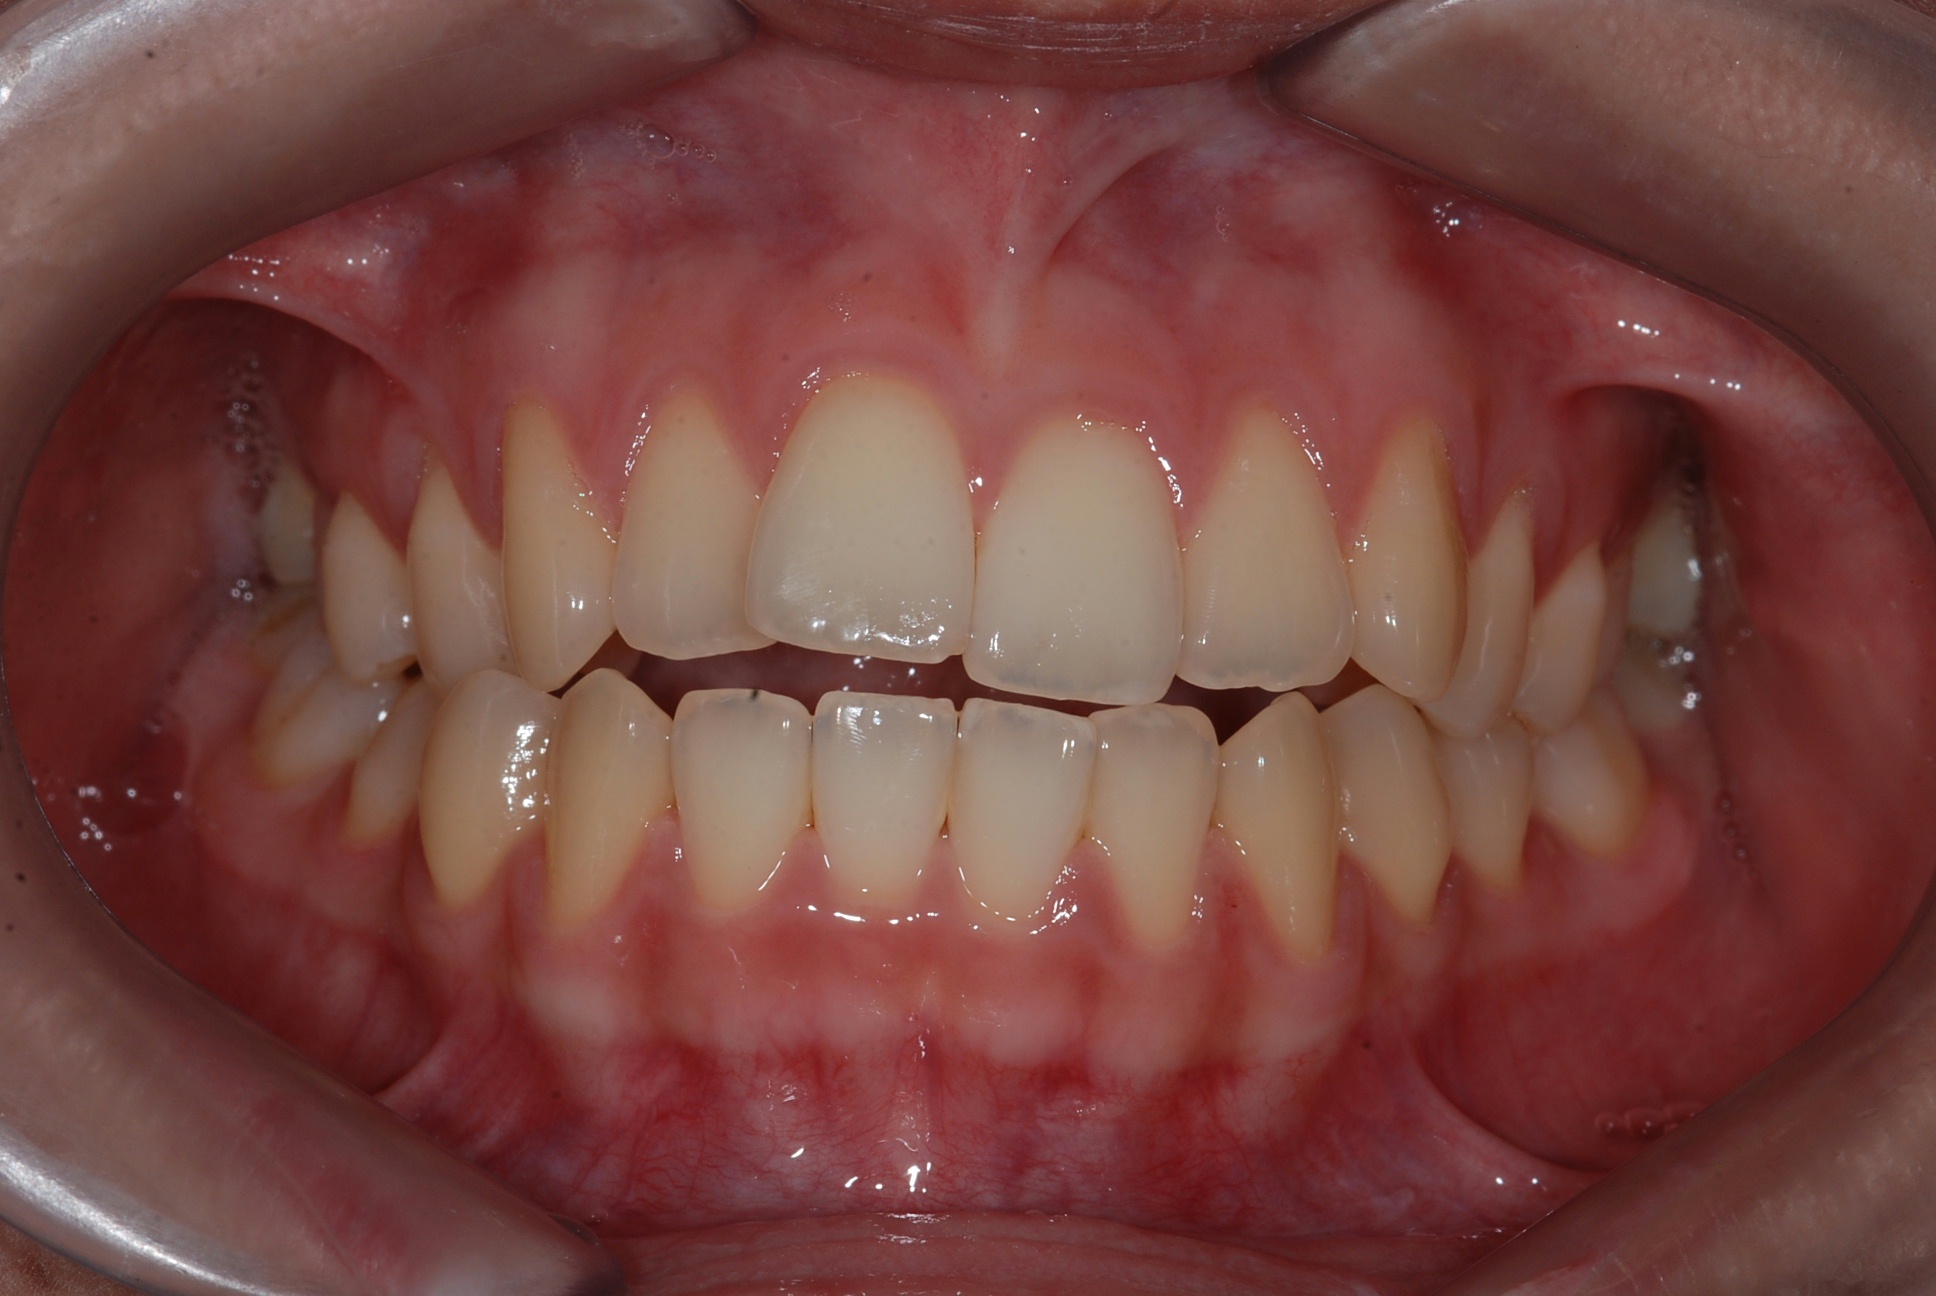

치료 후 사진입니다.